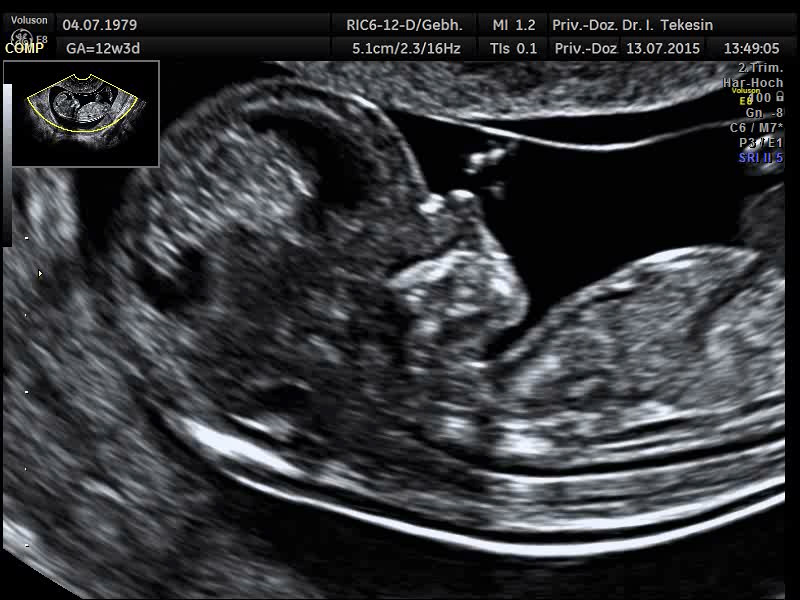

Kind in der 12. Woche

Kind in der 13. Woche